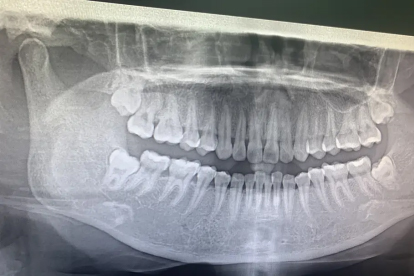

智齿的形成主要与人类颌骨进化及遗传因素有关,通常在17-25岁萌出,是第三磨牙的俗称。智齿萌出异常可能与颌骨空间不足、牙齿排列拥挤等因素相关,常表现为阻生、倾斜或部分萌出。

父母存在智齿阻生史时,子女智齿异常萌出概率较高。基因决定牙胚发育方向和颌骨大小,可能引发智齿横向或倒置生长。建议青春期后拍摄全景片评估智齿位置,提前干预。

智齿牙胚形成期受辐射、创伤或感染等因素干扰,可能造成牙根弯曲、牙冠畸形等发育缺陷。这类智齿易形成含牙囊肿或引发神经压迫,需通过CBCT检查明确解剖关系。